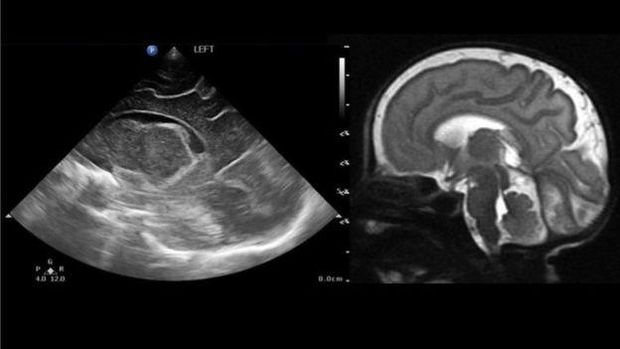

Sejauh ini dokter hanya bisa memberikan skrining dengan ultrasound untuk mengecek kondisi otak bayi yang baru lahir. Padahal bila dibandingkan dengan ultrasound, scan MRI jauh lebih akurat dalam memperlihatkan struktur otak dan abnormalitasnya, jika memang terjadi.

Sebaliknya, MRI dapat memfoto seluruh sudut otak dan anatomi di sekitarnya, sehingga gambar yang dihasilkan lebih jelas dan lebih mudah dipahami orang tua.

"Gambarnya lebih jelas terlihat dan lebih mudah dipahami ketimbang hasil ultrasound," kata Shaun.